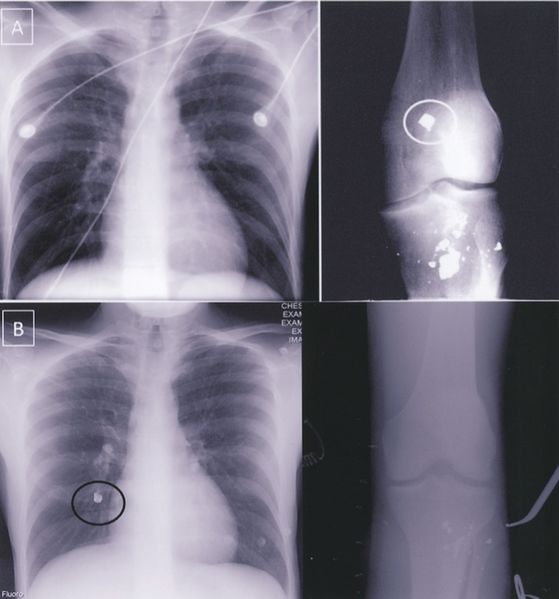

| current | 16:11, 2 August 2016 |  | 696 × 746 (86 KB) | Agarispe (Talk | contribs) | <ref name="variedpres"> Aidinian, G., Fox, C. J., Rasmussen, T. E., & Gillespie, D. L. (2010). Varied presentations of missile emboli in military combat. Journal of Vascular Surgery, 51(1), 214–217. http://doi.org/10.1016/j.jvs.2009.06.054 </ref> |